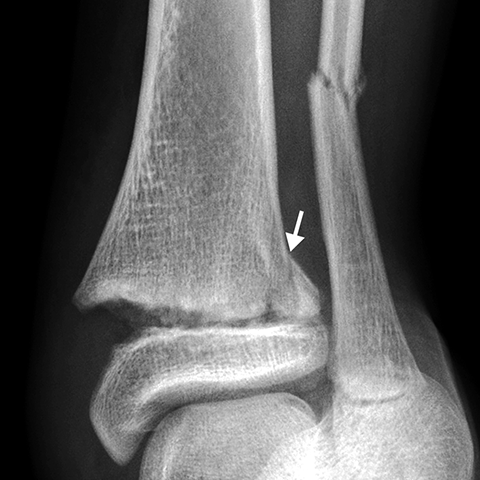

Salter-Harris fractures[3 of 3]